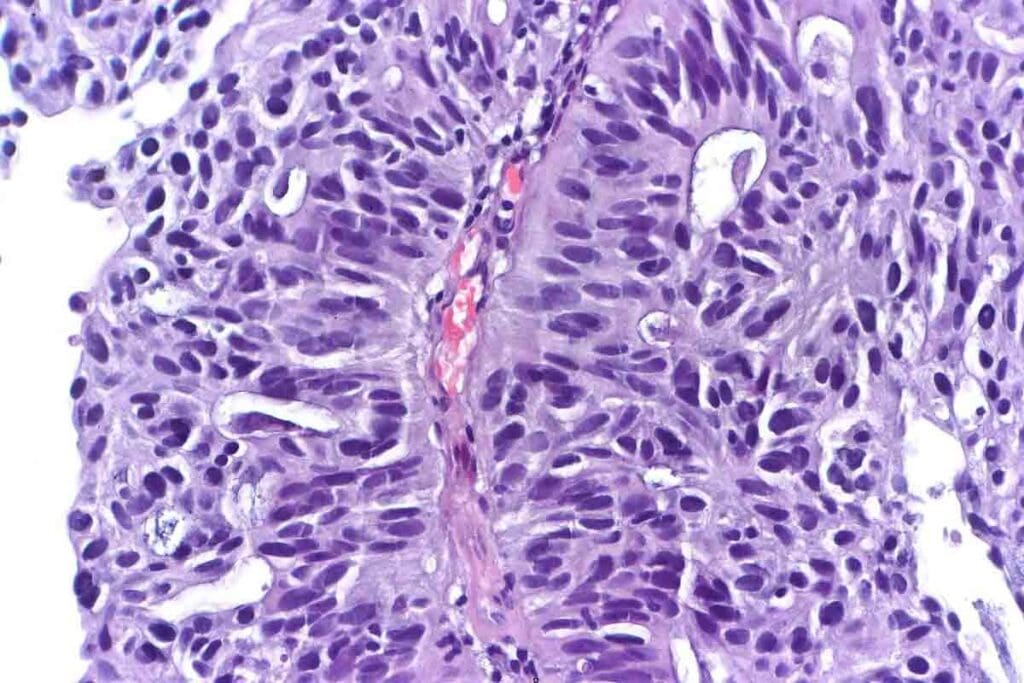

Biopsy and Pathological Confirmation

A biopsy is key to confirming ARMS. It involves taking a tumor sample for a microscope check. This helps spot ARMS’s unique features.

The sample also goes for genetic and molecular tests.